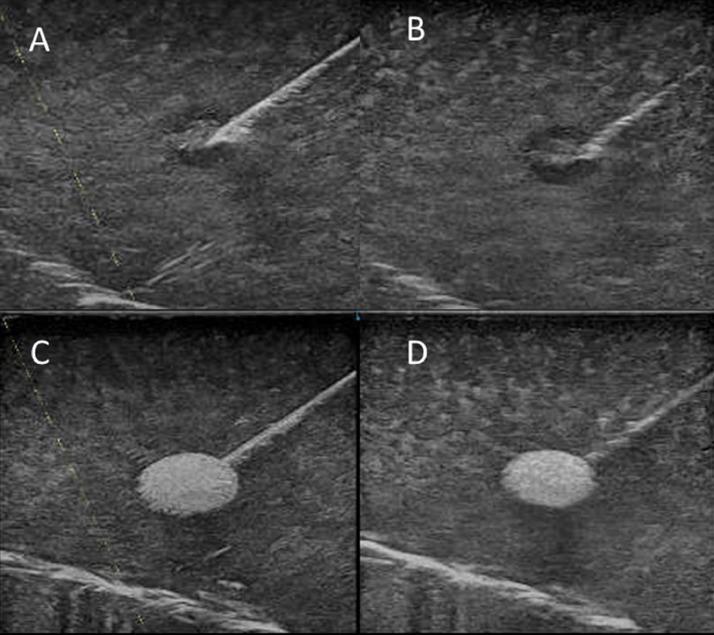

A useful case of ultrasound-guided axillary lymph node aspiration in a breast cancer patient with improved needle visibility.

Ultrasound-guided, lymph node, fine-needle aspiration cytology is important in diagnosing axillary lymph node metastasis in breast cancer. However, poor needle visibility can render the procedure difficult. We describe a case in which state-of-the-art enhancement techniques using matrix linear probes can provide better needle visibility and improve the certainty and efficiency of the examination.